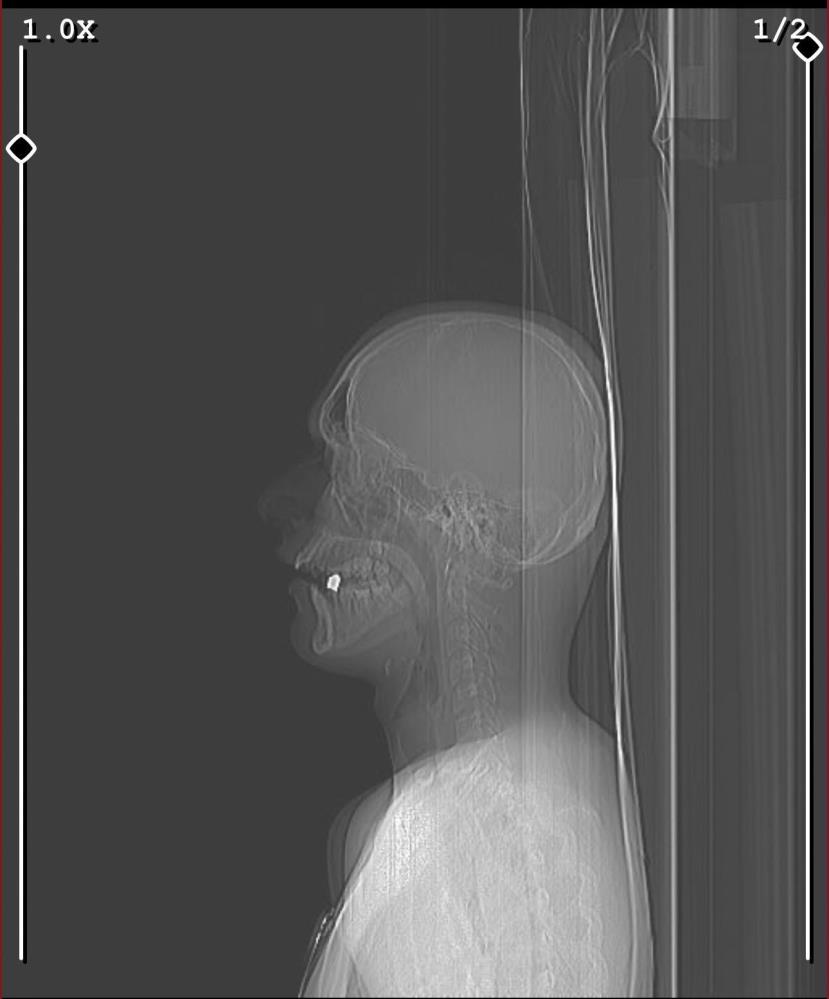

MAGANDA KURŞUNU BOYNUNDAN GİRDİ AĞZINDA KALDI!

Arkadaşlarıyla dondurma almaya giden 17 yaşındaki genç, cadde üzerinde seyir halinde oldukları aracın içerisinden rastgele açılan maganda kurşununun hedefi oldu. Kurşun 17 yaşındaki gencin boynundan girip ağzında kaldı. Ateş açan şahıslar ise olay yerinden kaçarak uzaklaştı.